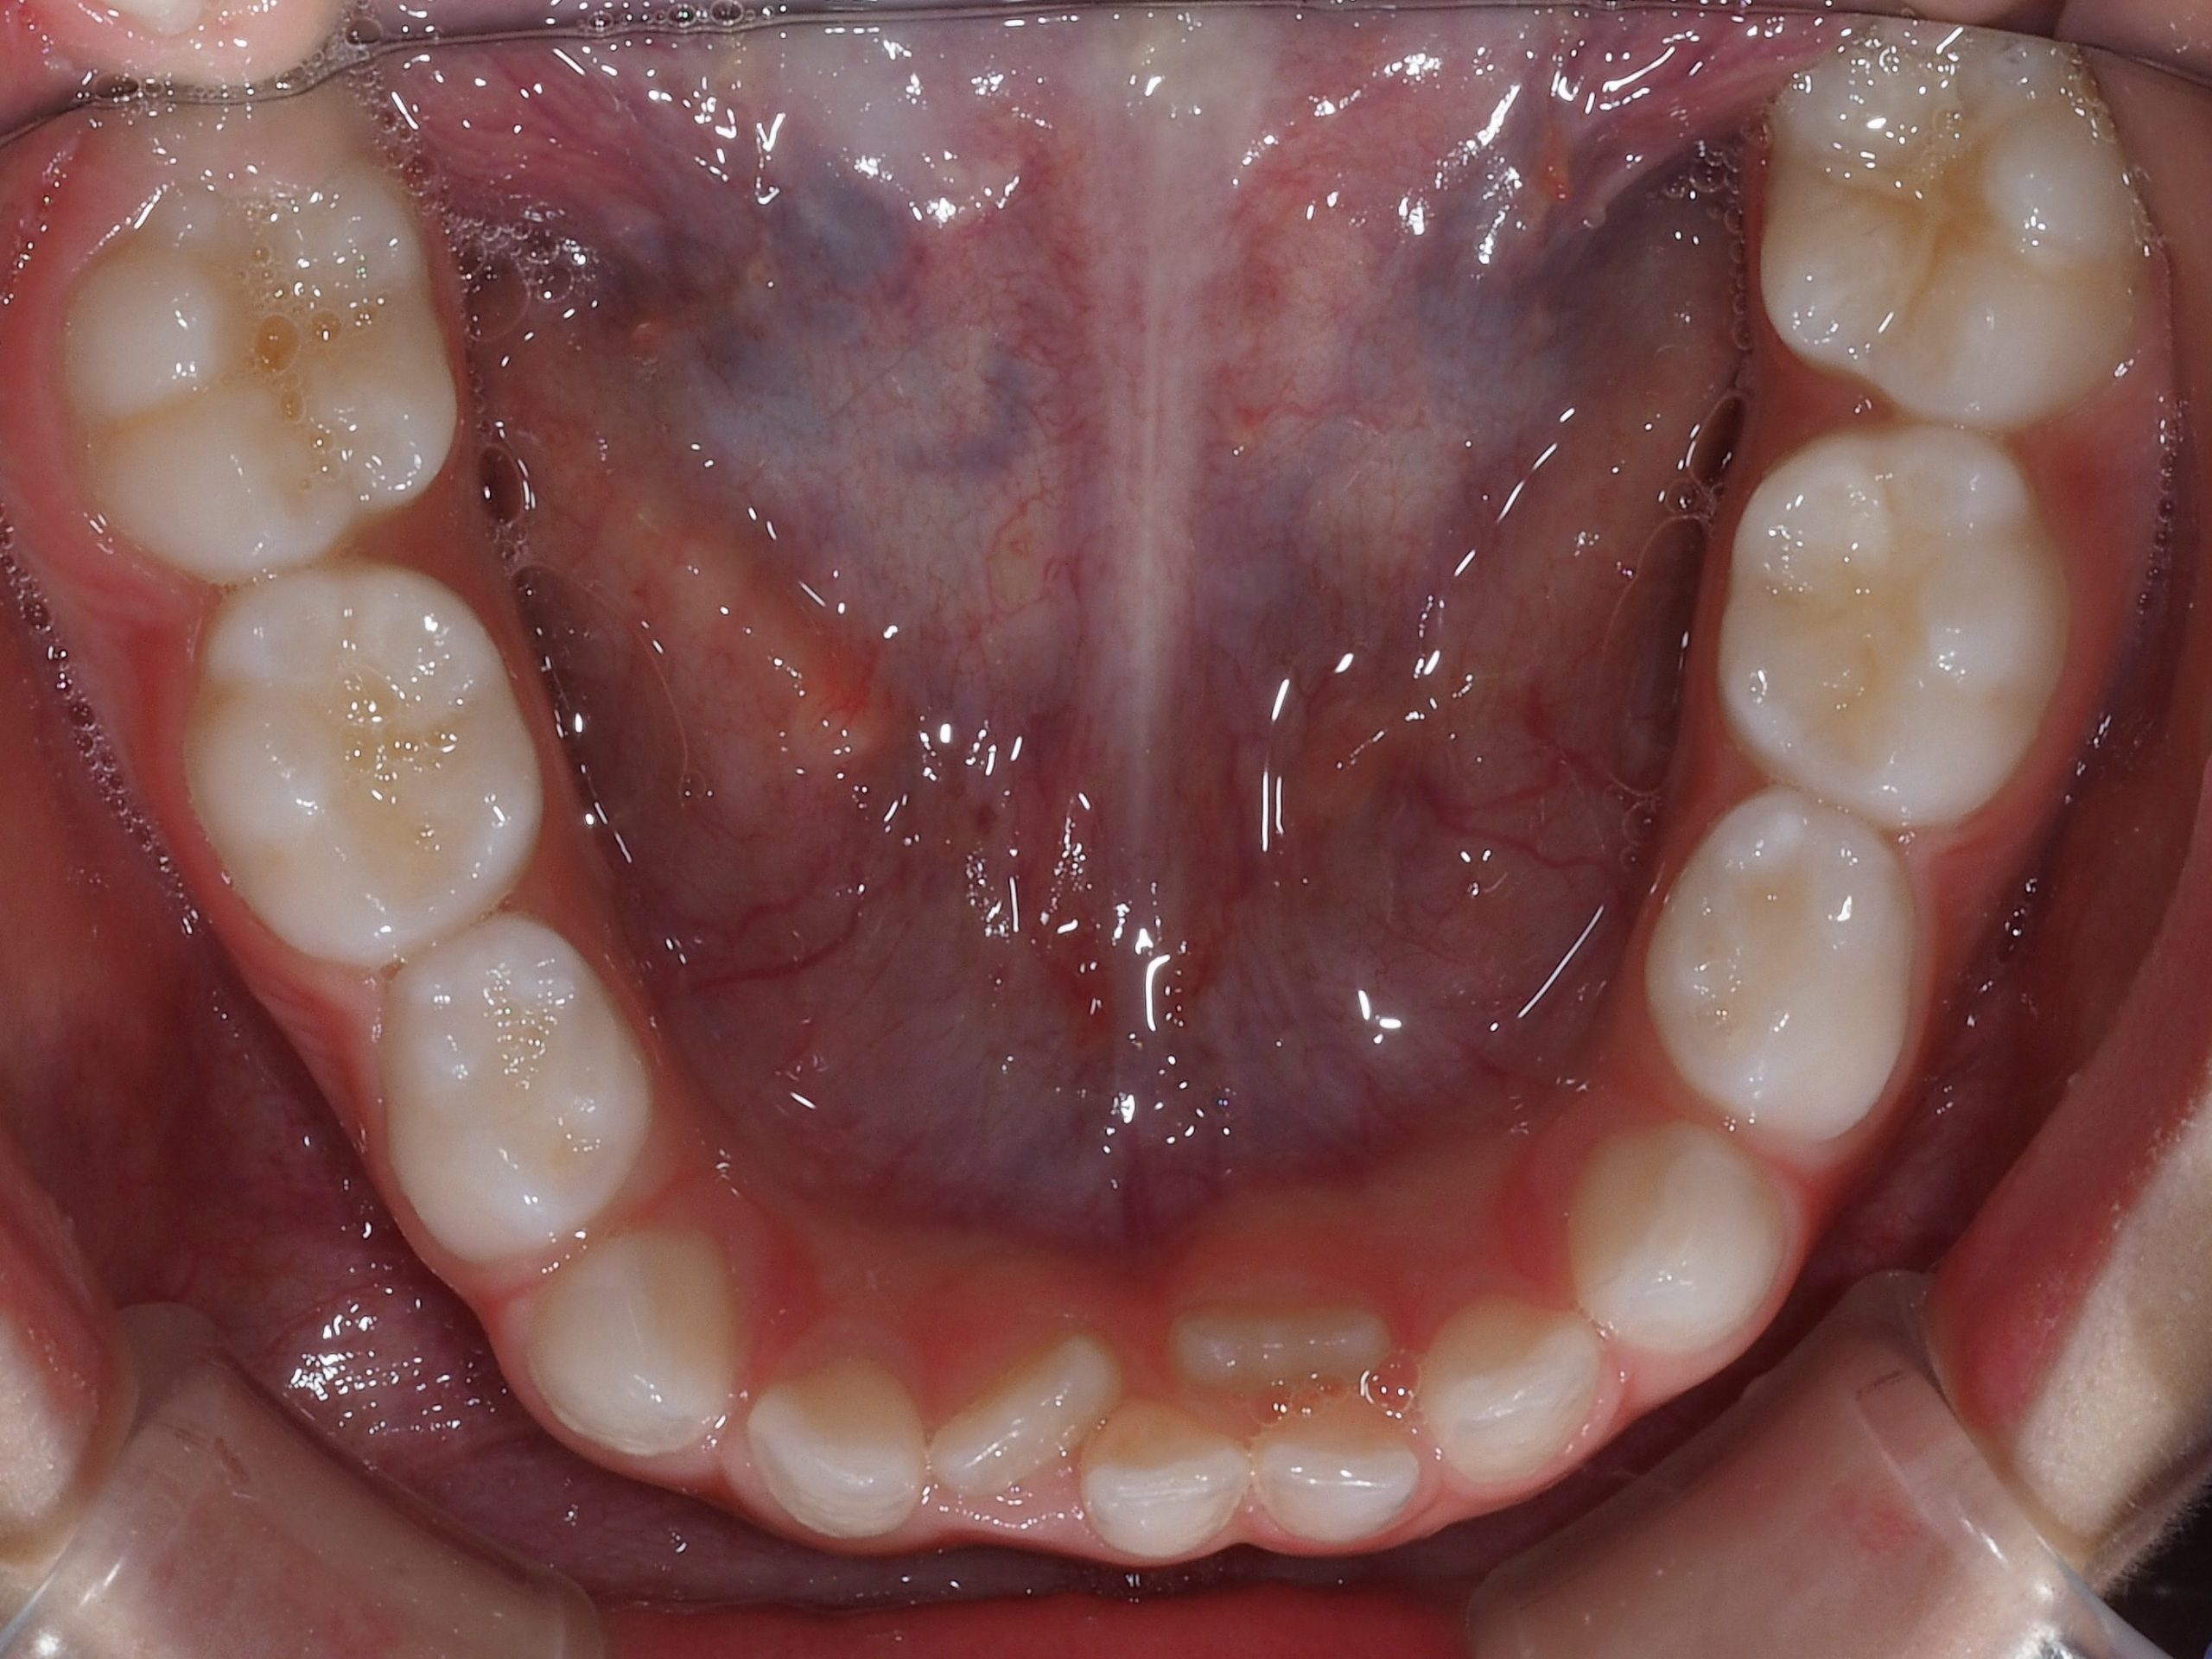

L’affollamento dentale dovuto alla mancanza di spazio nella bocca dei bambini è un problema molto comune durante la permuta dei denti. In questa fase, si verifica il cosiddetto fenomeno della dentizione mista, in cui i denti permanenti (soprattutto gli incisivi) vanno ad accavallarsi su quelli da latte, causando appunto un posizionamento dei denti in doppia fila.

L’eruzione dei denti permanenti può andare incontro a diverse problematiche, portando allo sviluppo di denti in doppia fila o storti:

- Spazio ridotto (bocca piccola).